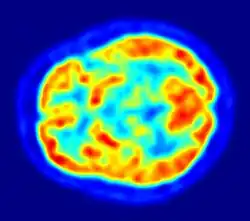

Ein Netz von über 100 Milliarden Kapillargefäßen, deren Gesamtlänge bei einem Erwachsenen ungefähr 600 km beträgt, durchzieht das gesamte Gehirn.[21] Der durchschnittliche Abstand dieser Blutgefäße beträgt 40 µm.[63] Die unterschiedlichen Hirnregionen werden unterschiedlich stark versorgt. Die Dichte an Kapillargefäßen ist in der Großhirnrinde (Cortex cerebri) mit 300 bis 800 Kapillarquerschnitten pro mm² Gewebe am höchsten.[1]

Mit der Positronen-Emissions-Tomographie werden zur Untersuchung der Blut-Hirn-Schranke im Wesentlichen die Efflux-Prozesse von potenziellen Wirkstoffen mit P-Glykoprotein dargestellt.[194] Das Verständnis der Funktion und der Beeinflussung von P-Glykoprotein an der Blut-Hirn-Schranke ist für die Entwicklung von Neuropharmaka von großer Bedeutung.[195] Diese rein wissenschaftlichen Untersuchungen werden mit Substanzen durchgeführt, die mit einem Positronen-Emitter (Beta-Plus-Zerfall (β+)) markiert sind. Dafür wird hauptsächlich das Isotop 11C verwendet. Bei fluorhaltigen Verbindungen wird bevorzugt das kurzlebige Isotop 18F eingesetzt. Wegen der sehr kurzen Halbwertszeit von 20,39 für 11C beziehungsweise 110 Minuten bei 18F können solche Versuche nur an Forschungseinrichtungen durchgeführt werden, in deren Nähe ein Zyklotron steht. Beispiele für entsprechend markierte und untersuchte Verbindungen sind Verapamil,[196] Carazolol,[194] Loperamid[197] und Carvedilol.[195] Verapamil ist dabei von besonderem pharmakologischen Interesse, da es in der Lage ist, P-Glykoprotein zu inhibieren.